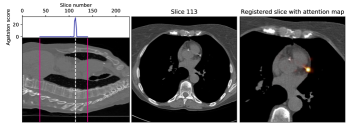

V-C Decision feedback

Decision feedback visualizes attention of the calcium scoring ConvNet. This feedback informs and end-user about the regions that contributed to the calcium score. Figure 7 shows examples of such feedback. The feedback helps an expert to quickly navigate and evaluate the image slices containing CAC.